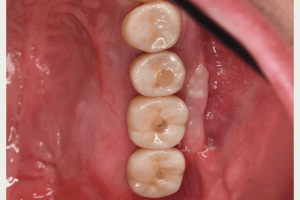

症例写真-2

- Befor

- 途中経過

- After

| 年齢 | 50代・男性 |

|---|---|

| 主訴 | 右下歯が疼く |

| 治療内容 | ・右下6番インプラント ※1:FGG(遊離歯肉移植術)とは、足りない歯ぐきを上顎から上皮を切り取り移植する外科手術 |

| 治療費 | 合計:902,000円(税込) ■内訳 |

| 治療期間 | 9ヵ月 |

| 治療方針 | 右下の当該歯は歯根破折により保存不可能と診断しました。歯周疾患も伴っていたため抜歯後に骨吸収※1が大きく起こることが予測できました。チタンメッシュ併用骨再生誘導法(GBR※2)を選択しインプラント埋入と同時に行い自然な歯槽骨のラインを再現しました。またGBRを行う際にインプラント辺縁の付着歯肉の減少が起こる為、遊離歯肉移植術(FGG※3)を行い清掃性を考慮した形態に仕上げました。 ■治療方針の解説 治療した右下の歯をレントゲンで撮影したところ根本の部分に黒く写る箇所があり「根尖性慢性周囲炎※1」と診断。また歯周病も進行していました。 ※1 骨吸収・・・歯槽骨という歯を支える骨がなくなっていくこと |

| 担当者所見 | 主訴の右下だけでなく歯茎の腫れ、発赤があり不良補綴や不良充填など他にも治療箇所が多数ありました。プラークコントロールが不良であった為まずはブラッシング指導を行いセルフケアの重要性を理解していただくところからスタートしました。 右下6番の歯はインプラント治療を行なった結果審美的にも機能的にも患者様の満足を得ることができました。骨造成と歯肉移植も行なった為インプラントを支える十分な歯周組織の獲得ができたと思っております。 |